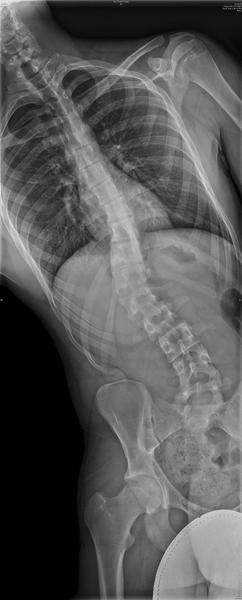

Hey guys, I don't post much here that much, some of you may not remember me or even know me. I have been very busy for the past few months with school and with my back. I have been dealing with scoliosis for over a year and a half now. And It turns out I first caught it after my growth spurt when I was 18. I had an x-ray and it was "supposedly" 15 degrees by stupid doctor number 1. It wasn't actually 15 degrees, it was 40 degrees and by 09, it had gone to 53*. Now my only option is a spinal fusion. It's really a big problem for me, it causes daily pain. I am having surgery Monday, December 28, 2009. I would just really like it if you guys wished me luck and kept me in your prayers so I have a safe surgery and have no problems. Thanks.

Here are some X-rays to show you how my spine looks.